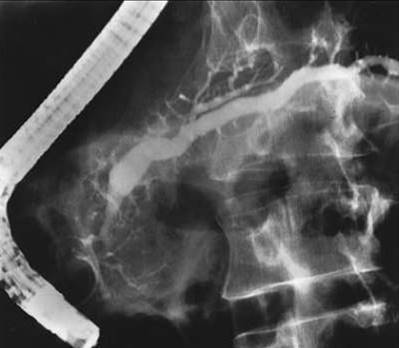

Рис. 6. Определяется расширение протока поджелудочной железы при хроническом панкреатите.